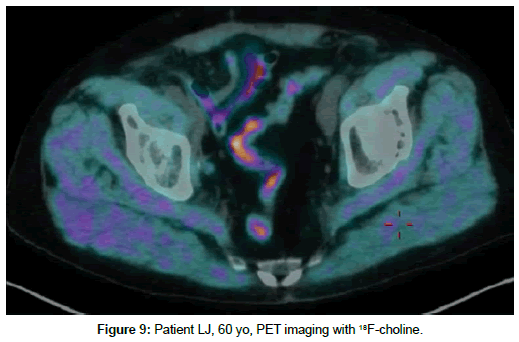

Patient LJ, 60 yo, prostate cancer treated with prostatectomy in 2013. Biochemical relapse, PET with 18F-choline on 30th September 2016 with serum PSA 0.79 ng/ml with no pathologic uptake (Figure 9). Second PET with 68Ga-PSMA on 26th October 2017 with seric PSA 1,56 ng/ml showed pelvic lymph node with strongly increased PSMA uptake (Figure 10).